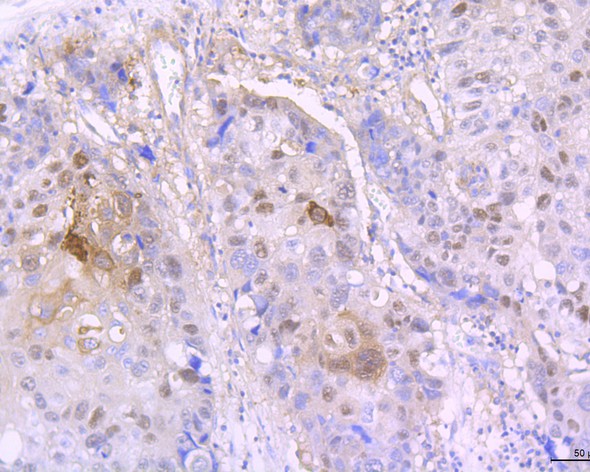

IHC-P